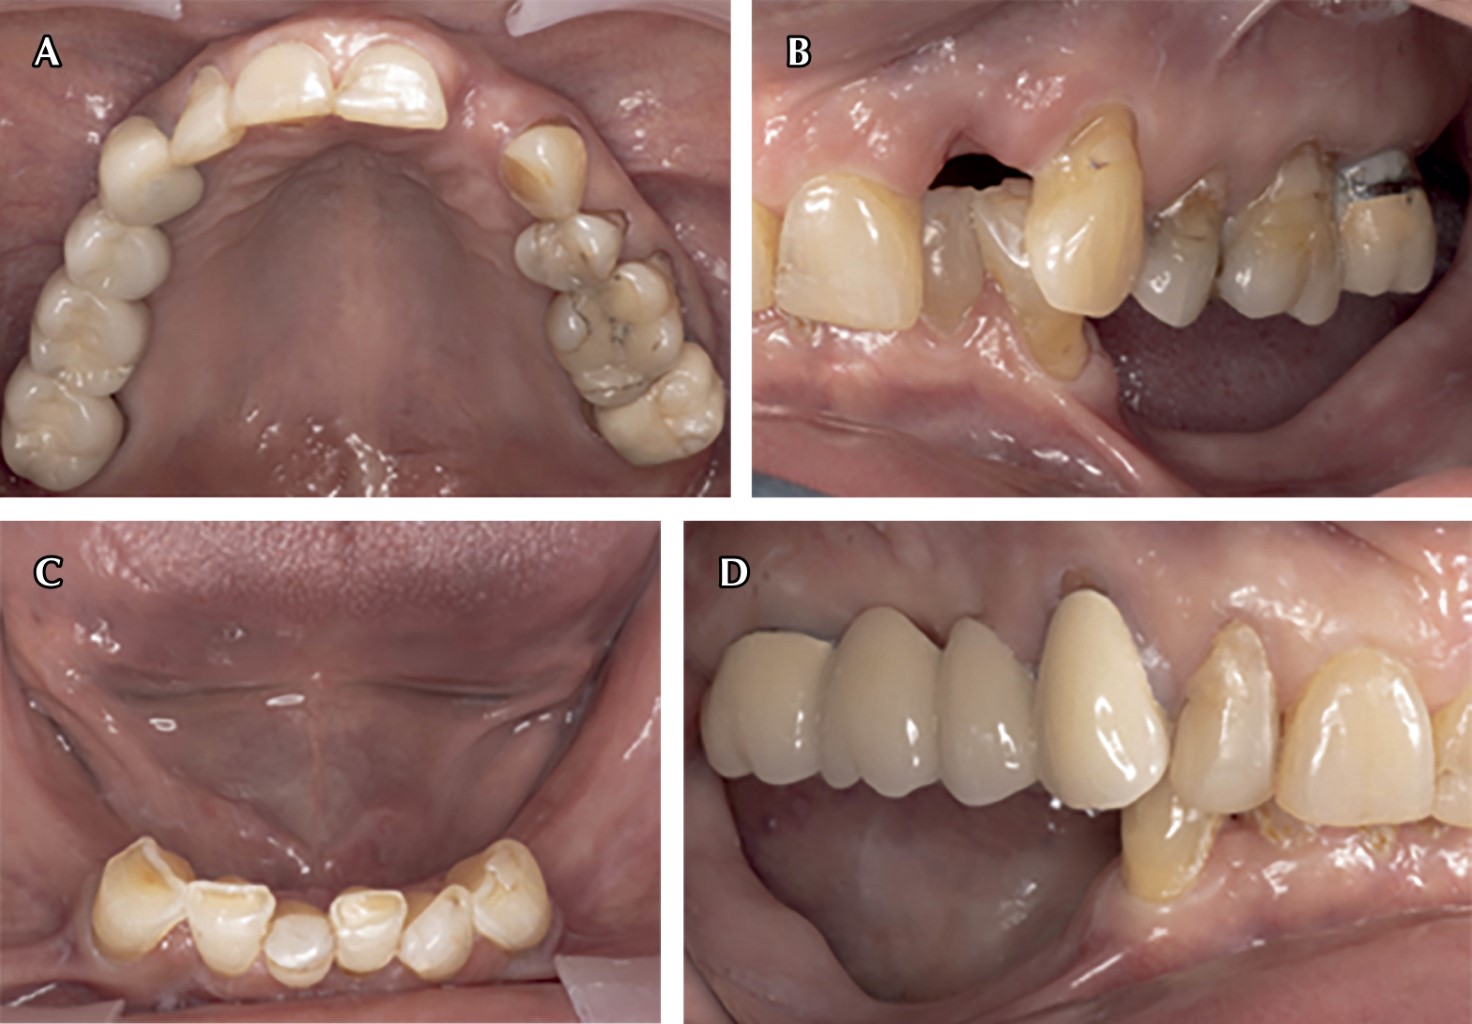

Bisphosphonates are synthetic analogue drugs of pyrophosphates that have a high antiresorptive potency in the bone remodeling cycle. They have in their chemical structure a carbon atom which remains linked to two phosphate groups (P-C-P), their negative charge explains the affinity they have for bone tissue. This clinical report presents the treatment of a patient with a history of osteoporosis, who, due to the use of removable partial dentures in poor condition, caused severe atrophy of the alveolar ridge. Currently, he is prescribed zoledronic acid (bisphosphonates). The placement of dental implants and extractions is contraindicated in patients on bisphosphonate treatment, so an alternative treatment is chosen that consists of a removable polyoxymethylene partial prosthesis and a four-unit bridge with an endocrown-type posterior abutment design. After one year, with 11 months of use of the new fixed prosthesis, the patient did not present dislodgement of the bridge, no occlusal problem was observed, with no absence of increase in the resorption of the edentulous alveolar ridge in the maxilla and mandible, the treatment gave great results both for the general health of the patient and to meet her expectations.

Figure 3